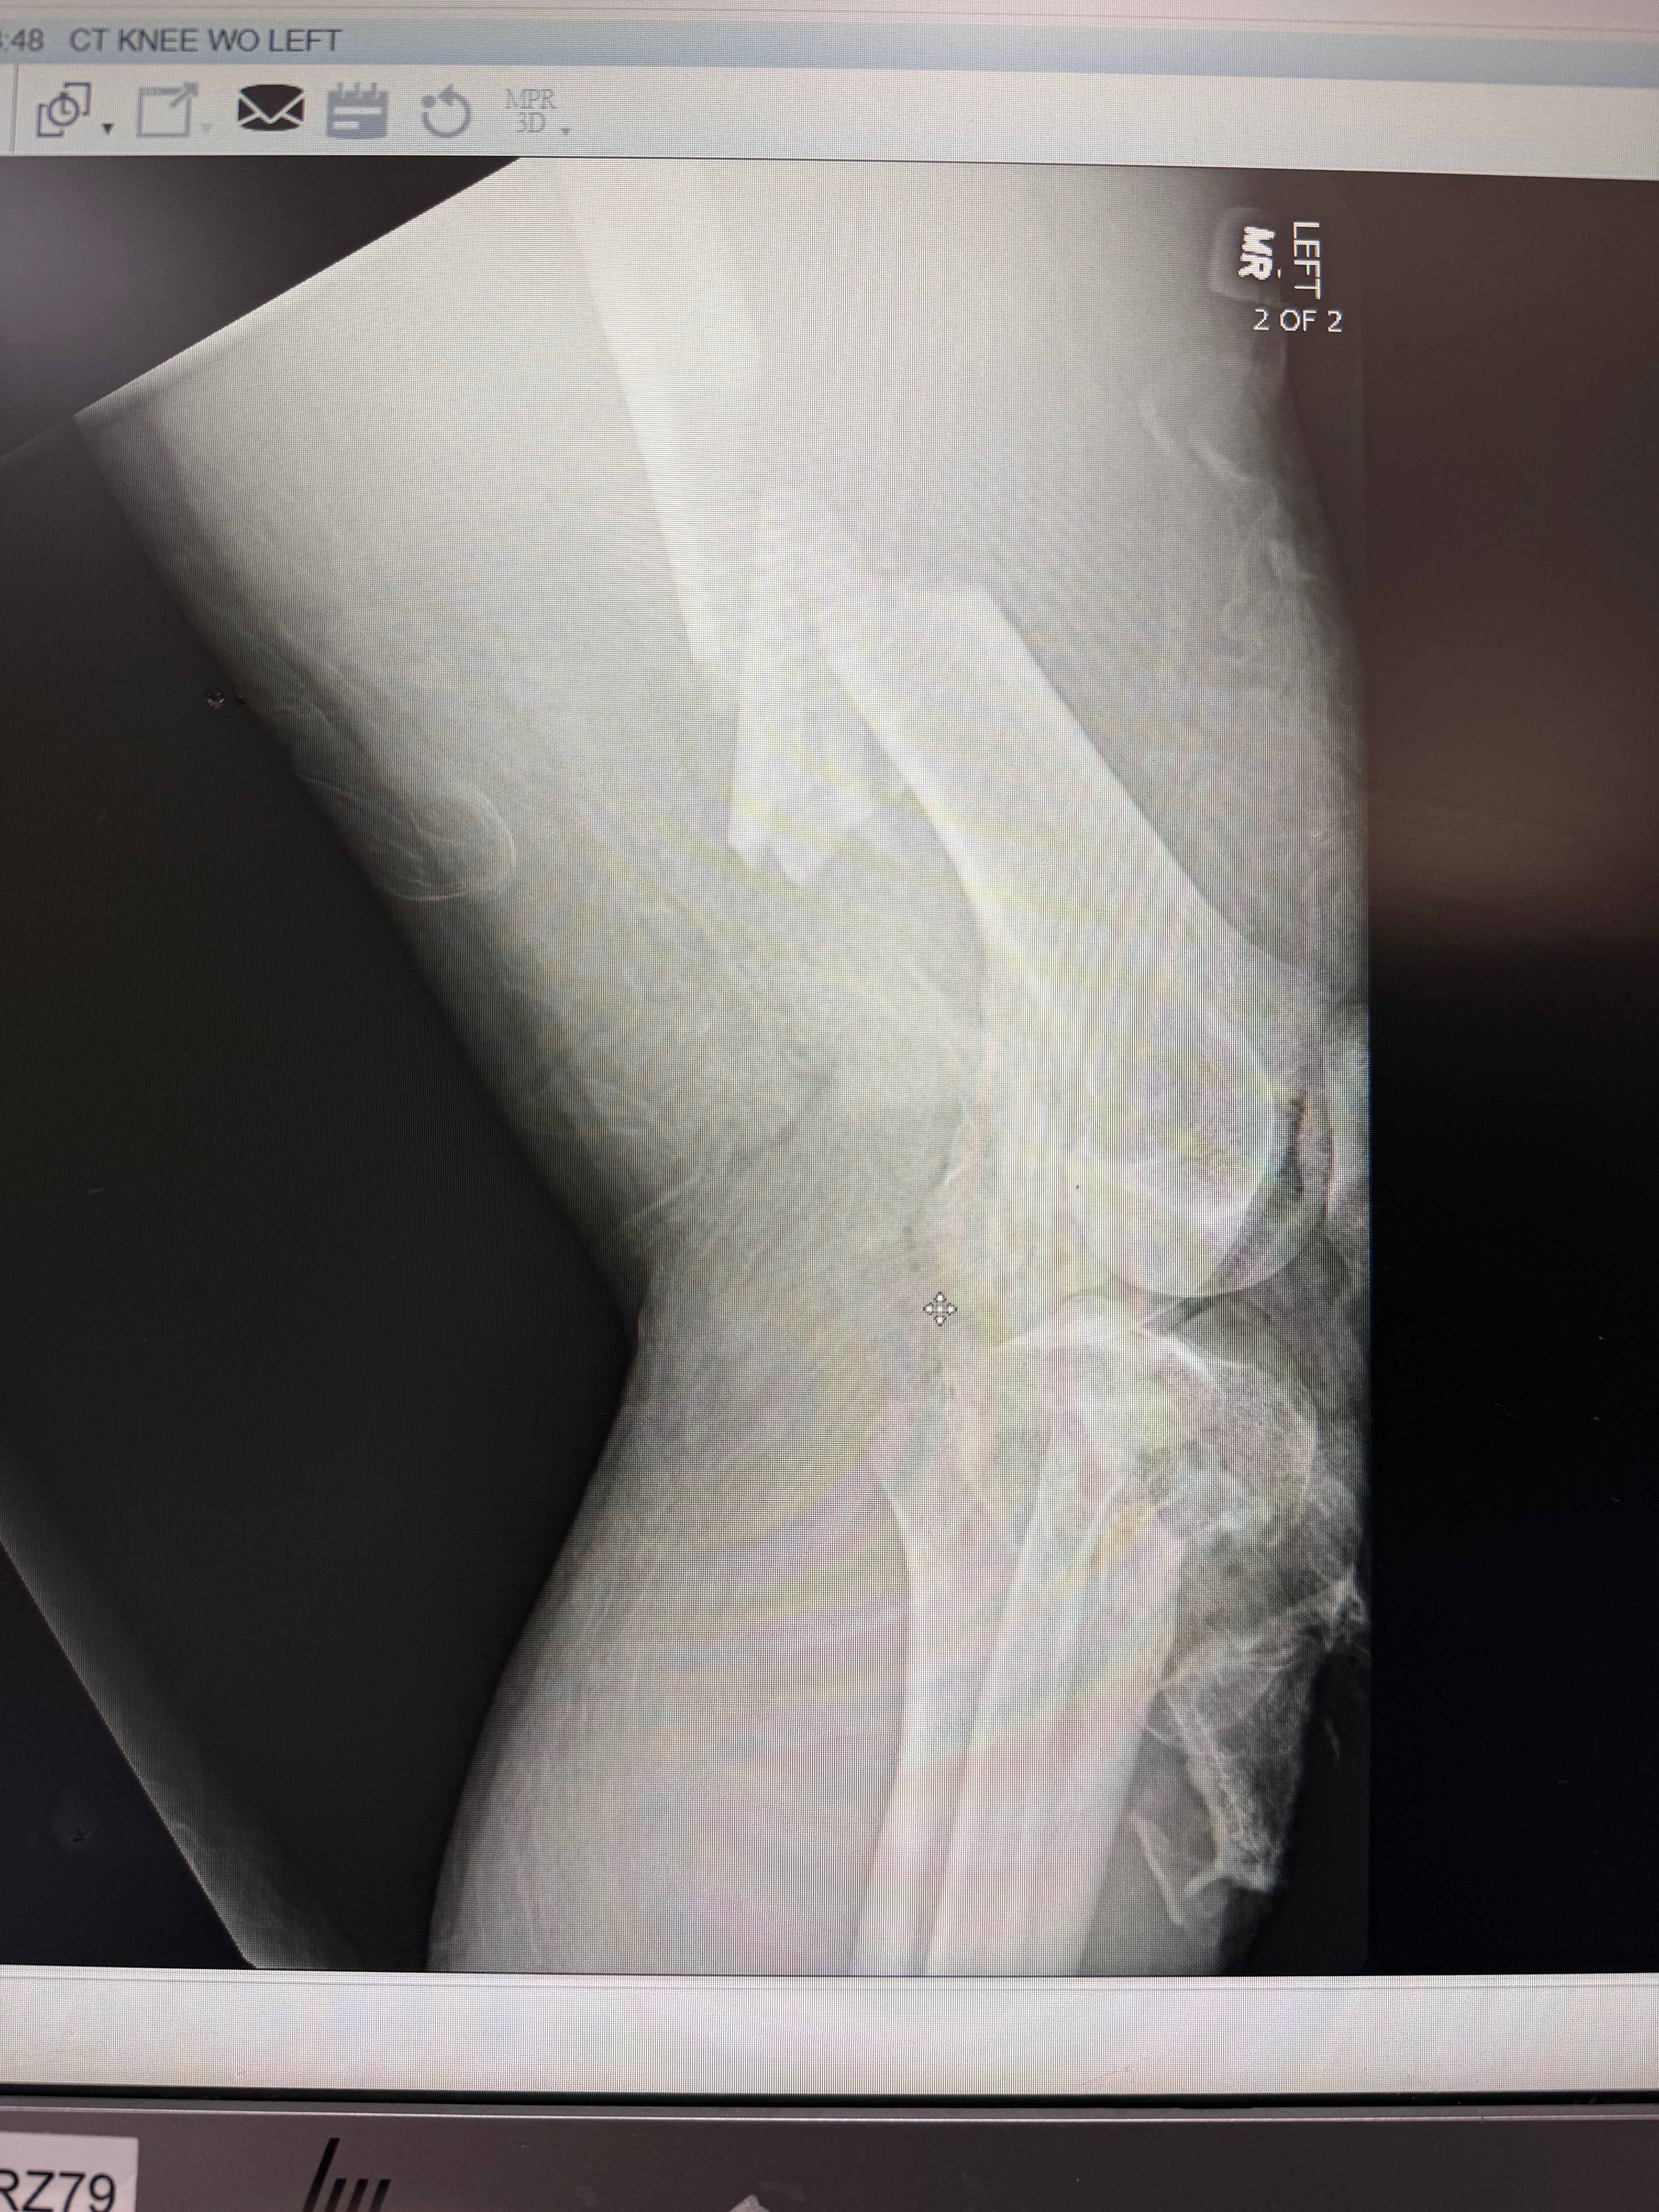

My name is Maxwell and I was involved in a very serious motorcycle accident on 12/29/2025 that left me with a shattered femur, tibia, and knee. I nearly bled out on the highway, and almost lost my leg in the OR.